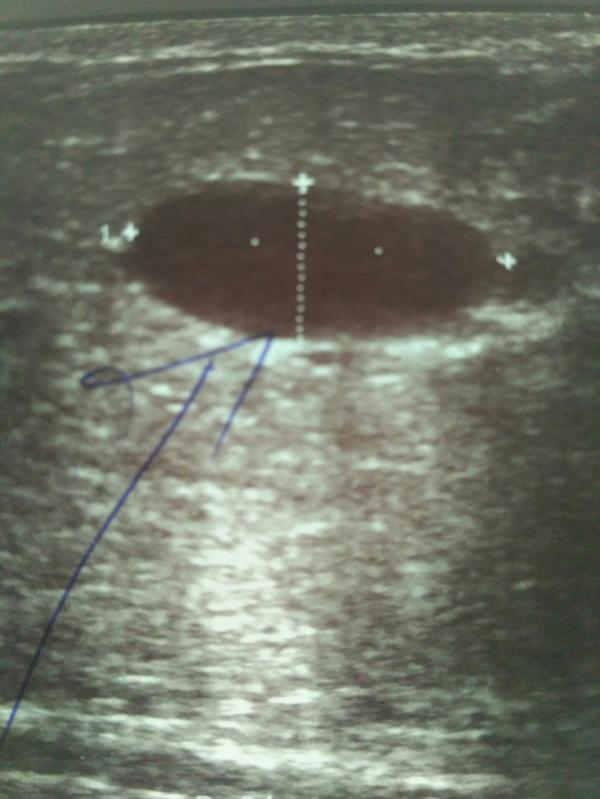

Во время кормления грудью в правой груди появилось уплотнение. Я думала это лактостаз и что дочь всё рассосет. Но не там то было. Пошла на УЗИ, размеры 16*9*15 мм. Отправили к онкологу делать пункцию. Пока неделю ждала результат думала сойду с ума, надумала там уже всего себе. Пришёл результат - это лактоцеле, ничего злокачественного нет, но нужно сворачивать гв и вырезать 'это' чтобы избежать образование раковых клеток. ...